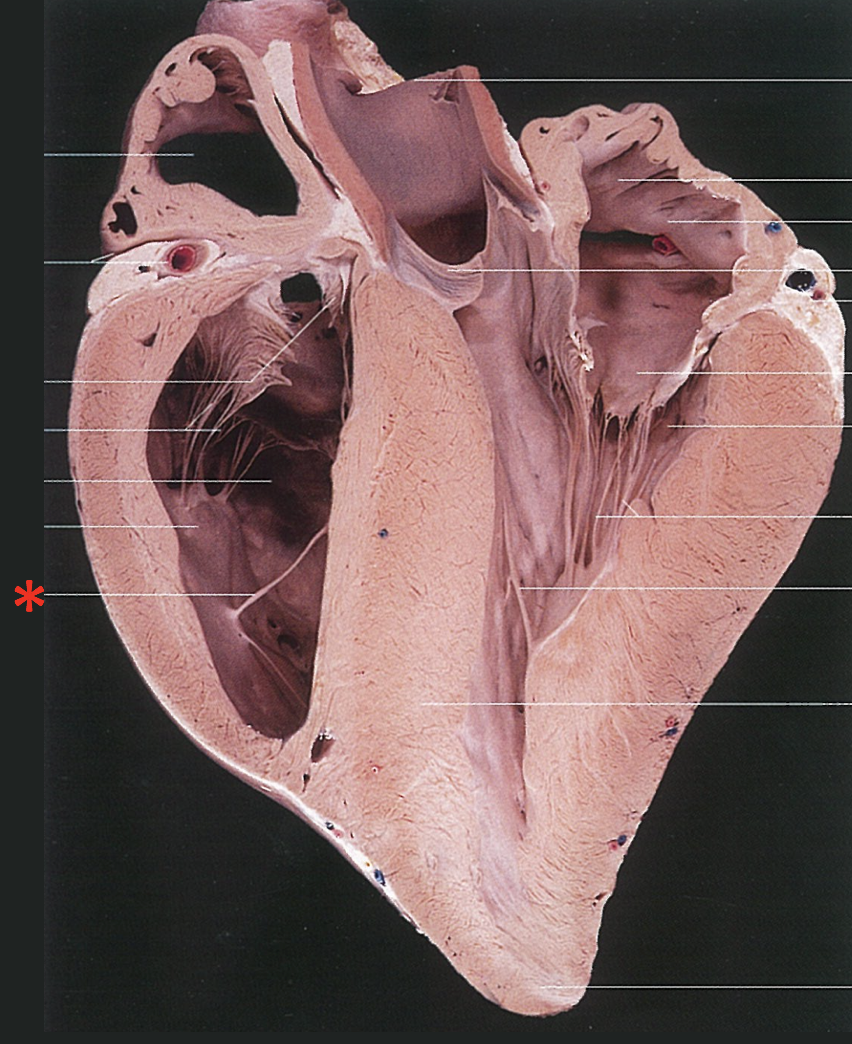

A

Chordae Tendinae

Left Muscular Band

Trabeculae septomarginalis sinistra

Right Muscular Band

Trabeculae septomarginalis dextra

Muscular Ridges

Trabeculae carneae